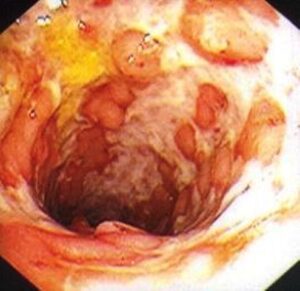

Identificata una sostanza chimica in grado di provocare le remissione della colite ulcerosa: a individuarla un team canadese del Farncombe...